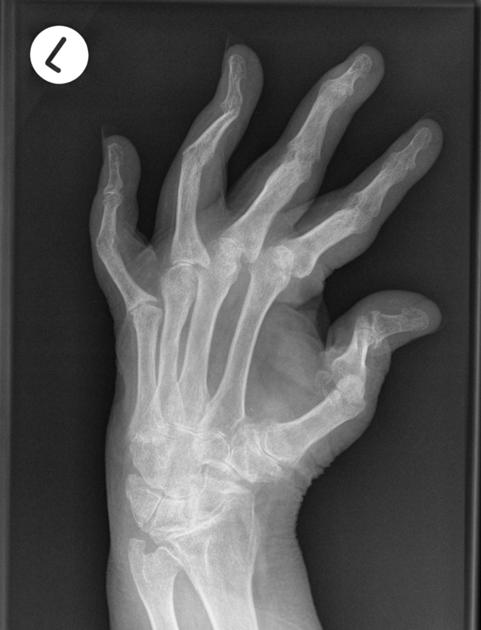

X-rays:

There are specific features that may clue a radiologist or rheumatologist to the presence of psoriatic arthritis. For example, the type of deformity that can be caused by psoriatic arthritis looks different from that of rheumatoid arthritis or osteoarthritis.